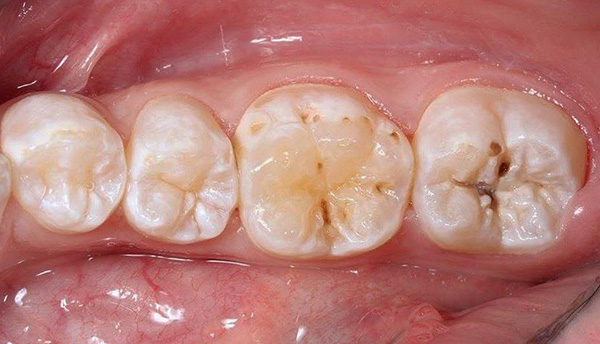

A foto abaixo mostra a cárie média localizada na região da fissura (fossa) dos molares:

Em casa, esses defeitos nem sempre podem ser identificados corretamente - eles podem parecer manchas acinzentadas ou marrons, pontos, ranhuras. Se esse defeito estiver no espaço interdental, pode ser difícil perceber. Defeitos nos molares pequenos e grandes inferiores são claramente visíveis (um exemplo é dado na fotografia abaixo).